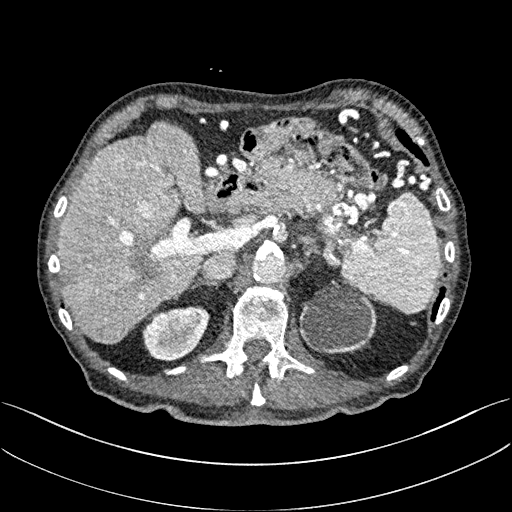

To demonstrate the effectiveness of the proposed network, we perform the qualitative comparisons over three representative abdominal images presented in Figs. 3, 5 and 7. For better evaluations of the image quality with different denoising models, zoomed regions-of-interest (ROIs) are marked by red rectangles and shown in Figs. 4, 6 and 8 respectively. Note that all results from different denoising models focus on two aspects: content restoration and noise-reduction. All CT images in axial view are displayed in the angiography window [-160, 240]HU.

The real NDCT images and corresponding LDCT images are presented in Figs. 3a and 3b. As observed, there are distinctions between ground truth (NDCT) images and LDCT images. Figs. 3a and 7a show the lesions/metastasis. Fig. 5a presents focal fatty sparing/focal fat. In Figs. 4a, 6a and 8a, these lesions can be clearly observed in NDCT images; in contrast, from Figs. 4b, 6b, and 8b, it can be seen that the original LDCT image is noisy, and lacks structural features for task-based clinical diagnosis. All adopted denoising models suppress noise to some extent.

To study the robustness of the adversarial learning framework in SMGAN-3D, we compared SMGAN-3D with the CNN-based methods, including CNN-L2, CNN-L1, RED-CNN [35], SL-net and MSL-net. It is worth noting that CNN-L2, CNN-L1, and RED-CNN are mean-based denoising methods, and SL-net and MSL-net are SL-based denoising methods. All of the methods greatly reduce the noise compared with LDCT images. Our proposed method preserves more structural details, thereby yielding better image quality, compared with the other five methods.

Mean-based methods can effectively reduce noise, but the side effect is impaired image contents. In Fig. 3c, -net greatly suppresses the noise, but blurs some crucial structural information in the porta hepatis region. Meanwhile, some waxy artifacts can still be observed in Fig. 6c. -net does not produce good visual quality because it assumes that the noise is independent of local characteristics of the images. Even though it retains high SNR, its results are not clinically preferable. Compared with -net, in Figs. 3d and 5d, it can been seen that -net encourages less blurring and preserves more structural information. However, as observed in Fig. 4d, it still over-smooths some anatomical details. Meanwhile, in Fig. 6d, there are some blocky effects marked by the blue arrow. The results obtained by RED-CNN [35] deliver high SNR but blur the vessel details as shown in Figs. 4i and 6i.

For SL-based methods, as observed in Figs. 3e and 5e, SL-net generates images with higher contrast resolution and preserves texture of real NDCT images better than -net and -net. However, Figs. 4e and 6e show that SL-net does not preserve the structural features well, and there still remain small streak artifacts. Subsequently, in Figs. 4e and 4f, SL-net and MSL-net have low frequency image intensity variance because SSIM/MS-SSIM is insensitive to uniform biases [49, 51]. On the other hand, -net preserves the overall image intensity, but it does not preserve high contrast resolution well as SL-net and MSL-net do.

From Figs. 7 and 8, we can see mean-based and SL-based methods work well with effective noise suppression and artifact removal. However, the illustrations in Fig. 8 show that these methods blur the local strutural features. Our proposed SMGAN-based methods present a better edge preservation than the competing methods.

Overall, the observations above support the following statements. First, although the voxel-wise methods show good noise-reduction properties, to some extent they blur the contents and lead to the loss of structural details because they optimize the results in the voxel-wise manner. Second, SL-based methods better preserve texture than mean-based methods, but they cannot preserve overall image intensity. Third, the results produced by the proposed SMGAN-3D demonstrate the benefits of the combination of two loss functions and the importance of the adversarial training [41, 42].

III-D2 Comparison with WGAN-based denoising methods

To evaluate the effectiveness of our proposed objective function, we compare our method with existing WGAN-based networks, including WGAN and WGAN-VGG. Considering the importance of clinical image quality and specific structural features for medical diagnosis, we adopted the adversarial learning method [41, 42] in our experiments because WGAN could help to capture more structural information. Nevertheless, based on our prior experience, utilizing WGAN alone may yield stronger noise than other selected approaches, because it only maps the data distribution from LDCT to NDCT without consideration of local voxel intensity and structural correlations. The observations demonstrate that the noise texture is coarse in the images, as shown in Fig. 4g and Fig. 8g, which support our intuition.

Indeed, the images of WGAN-VGG[37], as shown in Fig. 3j, exhibit better visual quality with respect to more details and share structural details similar to NDCT images according to human perceptual evaluations. However, Figs. 4j (marked by the red circle) and 6j (marked by the green circle) suggest that it may severely distort the original structural information. A possible reason is that the VGG network [47] is a pre-trained deep CNN network based on natural images, and the structural information and contents of natural images are different from medical images.

Compared with WGAN and WGAN-VGG, our proposed SMGAN-3D, as shown in Figs. 4l (marked by the red circle) and 6l (marked by the green circle), can more clearly visualize the metastasis and better preserve of the portal vein.

In Figs. 7 and 8, it can be found that the SMGAN-based methods can achieve better anatomical feature preservations and visual quality than other state-of-the-art methods.

The experimental results demonstrate that our proposed objective function is essential to capture more accurate anatomical details.

III-D3 Comparison with Image space denoising

To validate the robustness of DL-based methods, we compared our method with the image space denoising method. Figs. 4h and 6h show that BM3D blurs the low-contrast lesion marked by the red circle and smooths specific features marked by the blue arrow. In contrast, SMGAN-3D exhibits better on the low-contrast lesion and yields sharper features as shown in Figs. 4l and 6l.

III-D4 Comparison with 2D-based SMGAN network

In order to evaluate the 3D structural information, we compared SMGAN-3D with SMGAN-2D. As shown in Fig. 4l, our proposed SMGAN-3D generated the results with better subtle details than SMGAN-2D and enjoys more similar statistical noise properties to the corresponding NDCT images. The reasons why SMGAN-3D outperforms SMGAN-2D are follows. First, SMGAN-3D incorporates 3D structural information to improve image quality. Second, SMGAN-2D takes input slice by slice, thus potentially leading to the loss of spatial correlation between adjacent slices.

Figs. 7 and 8 demonstrate that the SMGAN-3D can be used to provide improved anatomical feature preservation over other state-of-the-art methods.

In summary, we compared our proposed methods with existing methods, and it can be clearly observed that SMGAN-3D achieves robust performance in noise suppression, artifact removal, and texture preservation. Note that we recommend the reader to see ROIs (in Fig. 4 and 6) or zoom in to better evaluate our results. To further validate the generalization ability of our proposed model, we conclude more details in Appendix A.